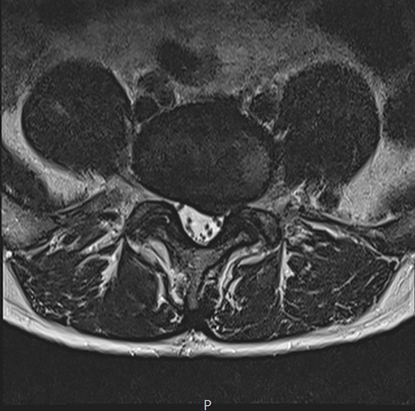

그림3.png 촬영 일시: 2025.04.30

<Fig 1. 좌측 협착증 및 디스크로 다리저림 및 허리통증 발생>

요추 5번-천추 1번 부위에

디스크 탈출과 협착증이 동시에 있었어요.

그것도 꽤 심한 정도로요.

신경이 정말 많이 눌려있는 상태였습니다.